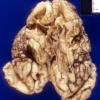

INFECTION

Herpes Simplex type II (HSV-2)